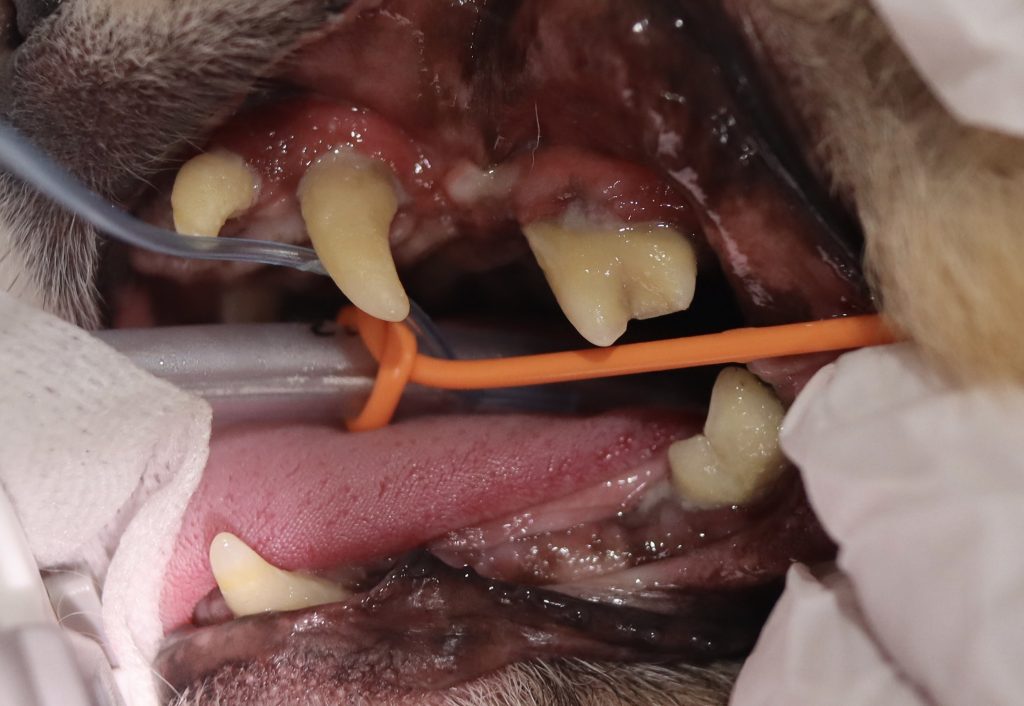

下の写真を見てみましょう。

全体的に歯垢や歯石が沈着し、歯肉が後退しているのが分かります。

特に、下顎犬歯に沈着している歯石を除去すると、歯根が見えるほど歯槽骨が融解していることが分かりました。